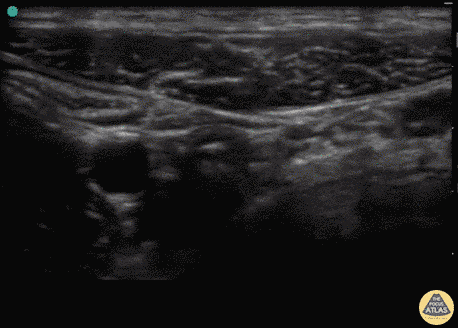

Bowel-GI - Normal Appendix (Transverse)

13 y/o F with several days of suprapubic pain, dysuria, nausea, vomiting, tender to palpation in the suprapubic and RLQ area. The appendix was visualized on both longitudinal and transverse views as a blind ended structure overlying the iliac vessels, a typical location for the appendix. In this view the iliac vessels and psoas muscle can clearly be visualized to the right of the appendix viewed in cross section. This study was eventually repeated and confirmed as normal. Dr. Sathya Subramaniam, Pediatric EM Fellow - Kings County/SUNY Downstate